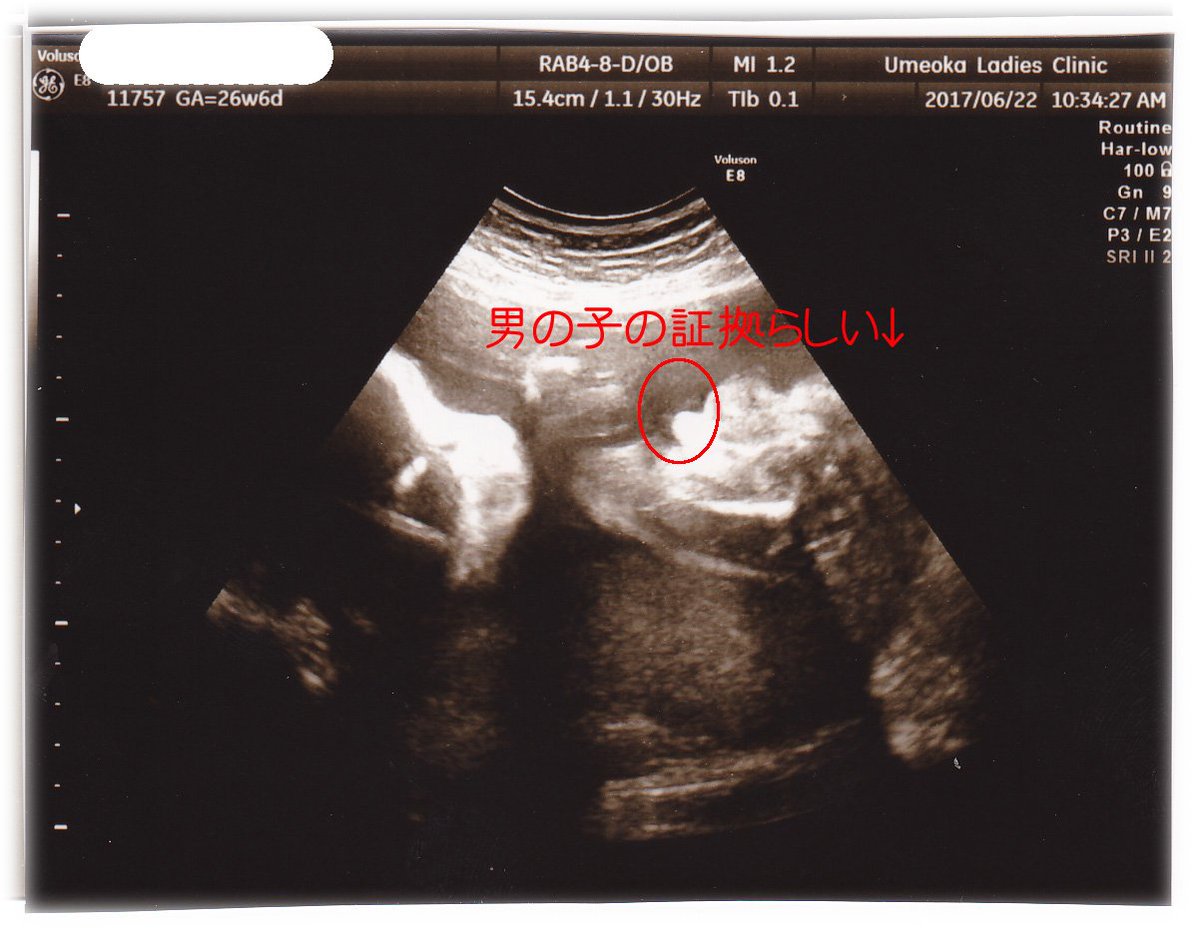

26w1d 妊婦健診 中期健診 女の子エコー有 トマトの妊活 妊娠 出産